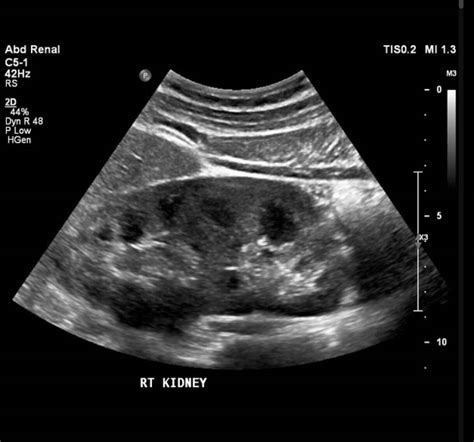

Vejiga ecografia posicion refers to the ultrasound examination of the bladder in different positions. This diagnostic tool uses high-frequency sound waves to create images of the bladder, helping healthcare providers assess its size, shape, and any abnormalities. The procedure is non-invasive and provides valuable information about the bladder's health and function.

After the vejiga ecografia posicion, the images are analyzed by a radiologist who looks for various indicators:

• Bladder Wall Thickness: Thickening of the bladder wall can indicate inflammation or other issues.

• Bladder Volume: The volume of urine in the bladder can help assess bladder function.

• Presence of Abnormalities: The presence of stones, tumors, or other abnormalities will be noted.

• Residual Urine: The amount of urine left in the bladder after voiding can indicate bladder outlet obstruction.

Some common findings in a vejiga ecografia posicion include:

• Bladder Stones: These are hard deposits that can form in the bladder and cause discomfort or infection.

• Bladder Tumors: Abnormal growths in the bladder that may be benign or malignant.

• Bladder Diverticula: Outpouchings of the bladder wall that can trap urine and lead to infections.

• Bladder Outlet Obstruction: Conditions that block the flow of urine from the bladder, such as an enlarged prostate in men.